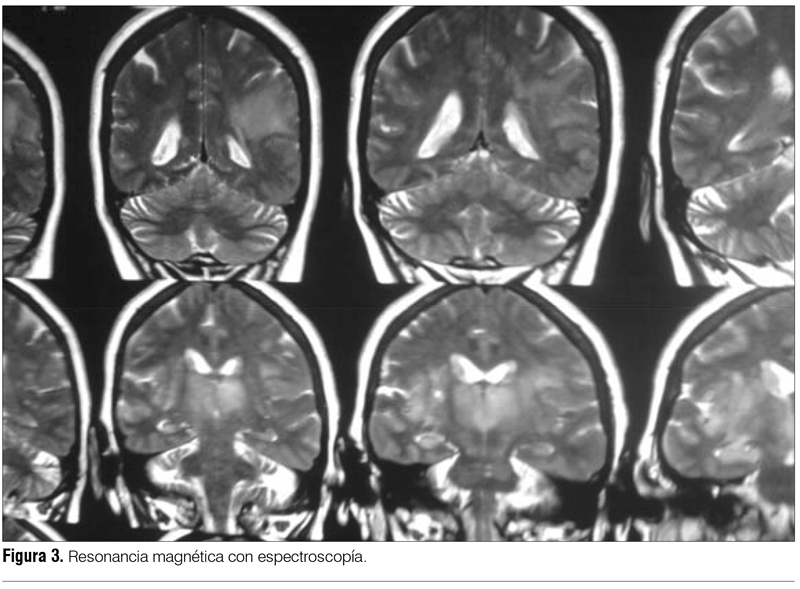

RM de cráneo con perfusión y espectroscopía informa extensa área infiltrativa a nivel de la sustancia blanca fronto-temporal derecha que cruza la línea media a nivel del cuerpo calloso e infiltra el lóbulo frontal izquierdo (figuras 2 y 3). Se afectan ambos tálamos con extensión al pedúnculo cerebral izquierdo hasta protuberancia y otra zona a nivel del carrefour témporo-parieto-occipital izquierdo. Secuencia de perfusión: realce de contraste heterogéneo a nivel frontal parasagital izquierdo. Secuencias de espectroscopía: zonas con disminución del N-acetil aspartato con pico de lípidos-lactatos. Estas características orientan a lesión tumoral primaria del SNC, probable gliomatosis cerebri. Biopsia esterotáxica informa proliferación tumoral maligna primitiva del SNC de estirpe glial de la serie astrocitaria, con moderada anisocariosis y anisocitosis compatible con gliomatosis cerebri. Presenta mala evolución clínica con depresión de conciencia, no iniciándose tratamiento oncoespecífico, se realizan medidas de confort. Fallece a los dos meses del diagnóstico.

La RM con espectroscopía es usada recientemente para evaluar si estamos ante una enfermedad estable o progresiva, mostrando un incremento de los niveles de glicina/inositol, siendo de utilidad como factor pronóstico(3,9).